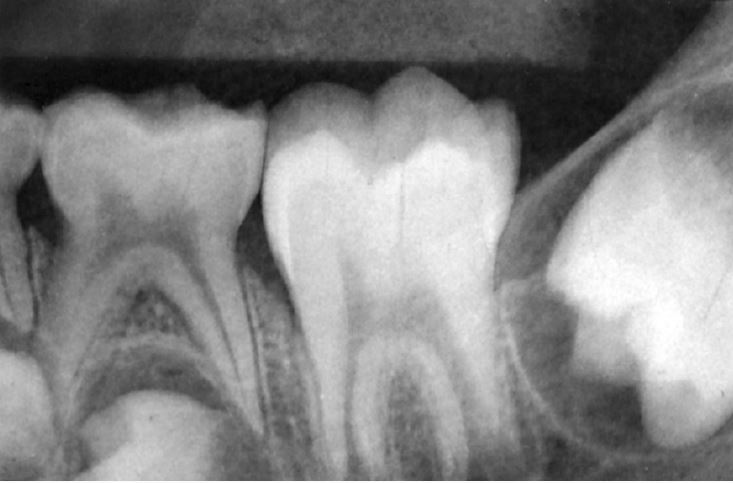

A radiograph reveals a radiolucency associated with the apex of tooth 1.5. There is a large restoration but the tooth is asymptomatic and the associated soft tissues appear normal. What is the most likely diagnosis?

Chronic periradicular periodontitis.NDEB released questions part 2 set 1